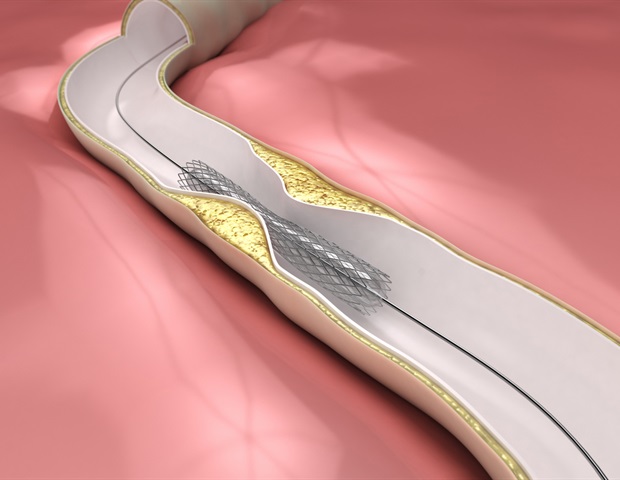

בלון חדש המוציא תרופות יכול לבצע בדיוק כמו הטיפול הסטנדרטי בחולים עם restenosis כלילית (ISR) העוברים התערבות כלילית חוזרת ונשנית